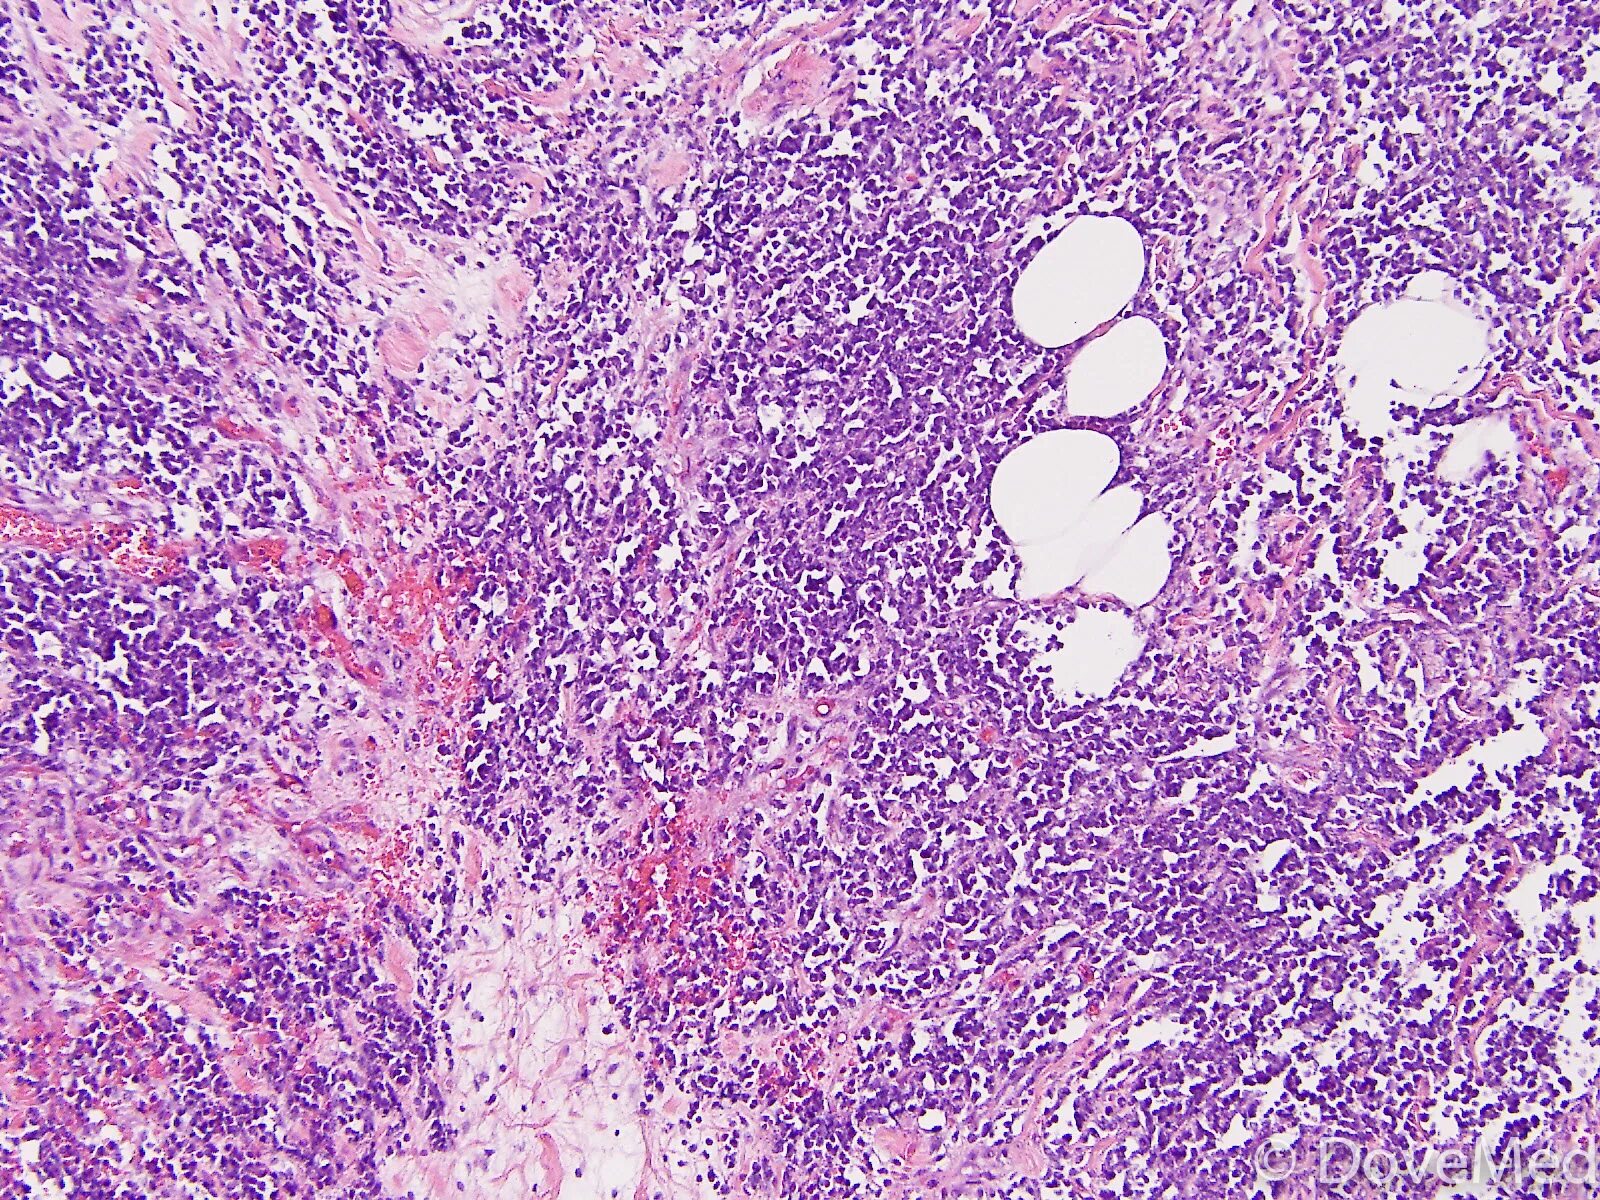

Лимфомы тесты